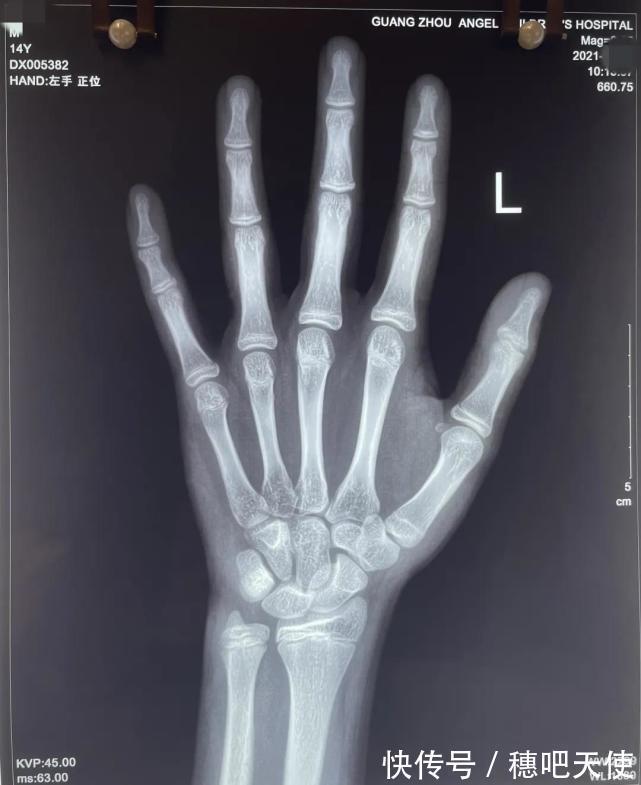

空腹采血、X光、B超、核磁共振、身高预测,我失魂落魄拿着各种单据,带着儿子在医院里穿梭。儿子的检查结果也无法让我彻底松口气——手部X光测骨龄显示12-13岁,略超正常范围,采血查激素全部正常,B超显示睾丸发育在正常范围内但偏大,核磁共振排除了脑垂体病变导致的发育异常。